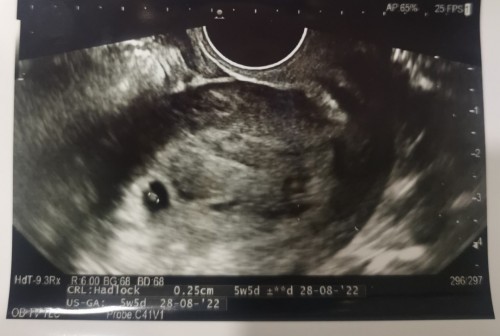

Larger yolk sac at 5 week 5 day

Hi everyone. Went for my gynae visit (2nd visit) and had a vaginal scan. Baby has grown a little bit since exactly one week ago (currently measuring 5 week 5 day) but doctor is concerned about a larger yolk sac (which could mean baby not absorbing enough). Has anyone had this and went on to a smooth pregnancy? I had a mc last year end and has been ttc-ing since then. Really anxious. Does my ultrasound look normal? Going back for a follow up in one week time.